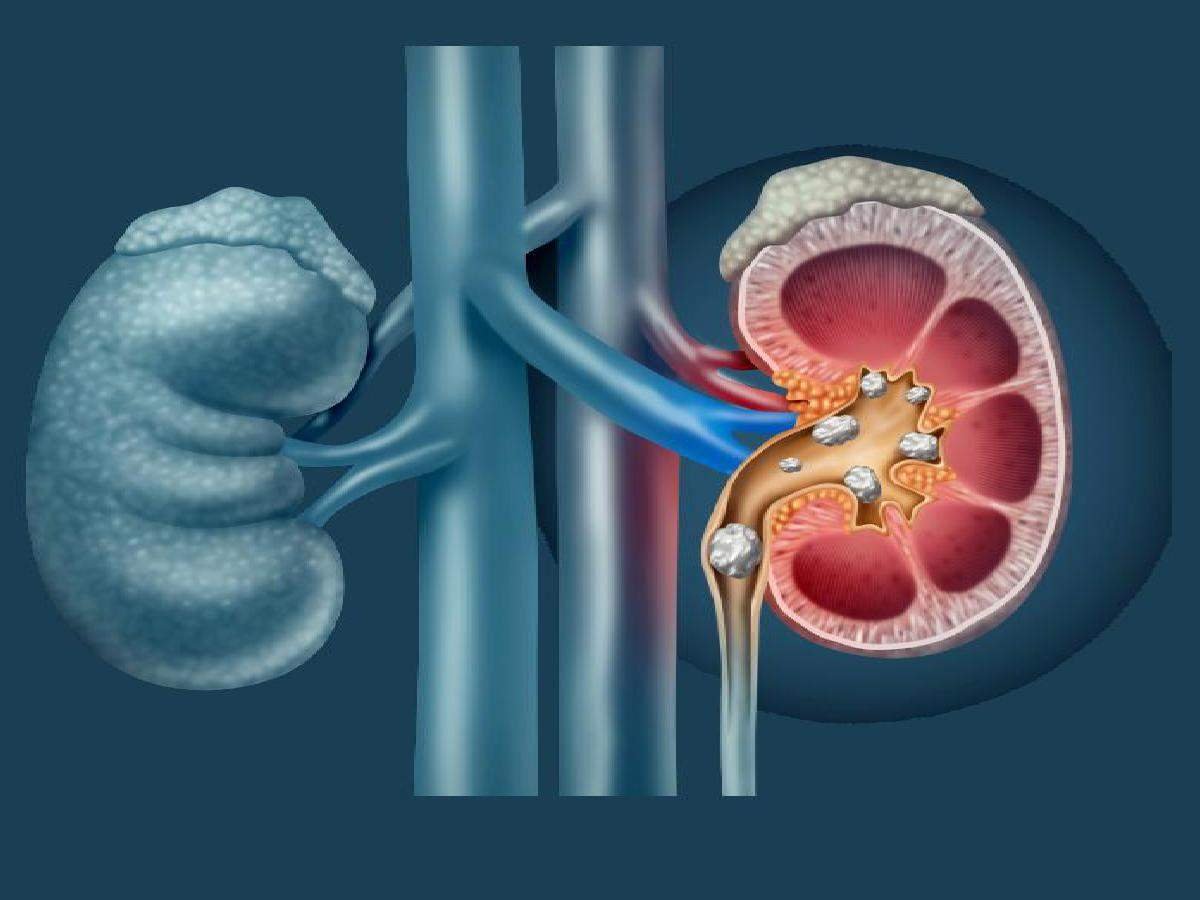

किडनी हेल्थ को मेंटेन रखने में

किडनी से जुड़ी कई प्रकार की बीमारियां इतनी जानलेवा होती हैं कि अगर उनका सही समय पर इलाज न किया जाए तो वह अन्य कई बीमारियों को भी निमंत्रण दे सकती हैं। एक वैज्ञानिक अध्ययन के अनुसार किडनी हेल्थ को मेंटेन रखने के लिए कुछ खास फूड्स की श्रेणी में पंपकिन सीड्स को भी शामिल किया गया है। इसलिए आप चाहें तो किडनी से जुड़ी बीमारियों के खतरे से बचे रहने के लिए पंपकिन सीड्स का सेवन कर सकते हैं।